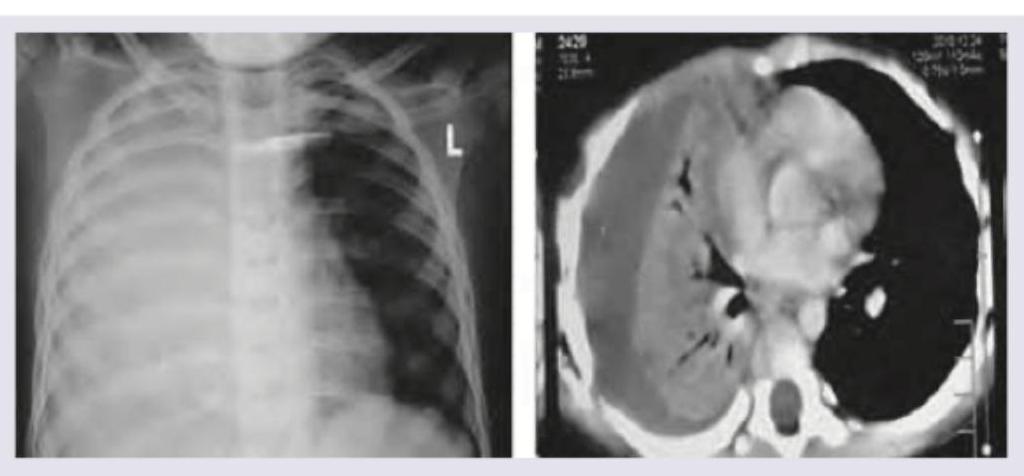

A 4-year-old child with high grade fever with chills and rigors for past 4 days and fast breathing is brought to the hospital. On examination subcostal recession and nasal flaring is noted. Since patient is already on antibiotics for past 3 days from another hospital a Chest X-ray and CT Chest was ordered. The diagnosis is:

Explanation: ***Massive right sided parapneumonic effusion*** - The chest x-ray shows complete opacification of the right hemithorax with a **mediastinal shift to the left**, indicating a large volume of fluid in the right pleural space. - The CT scan confirms a large, homogeneous fluid collection on the right side, compressing the lung and mediastinum, consistent with a **massive pleural effusion**, likely parapneumonic given the clinical context of fever and respiratory distress despite antibiotics. *Massive pan consolidation* - While consolidation would appear opaque on X-ray, **massive pan consolidation** of an entire lung would typically not cause such a significant **mediastinal shift** as fluid does. - The CT images show a distinct **fluid-density collection** rather than diffuse parenchymal opacification characteristic of consolidation. *Right sided hydro-pneumothorax* - A hydro-pneumothorax would present with a **fluid level** on the chest X-ray and CT scan, indicating both air and fluid in the pleural space. - The images show a **homogeneous fluid collection** without any discernible air component or fluid level, ruling out pneumothorax. *Right sided segmental collapse* - Segmental collapse would typically involve only a portion of the lung and would manifest as a **volume loss** in a specific segment, often with features like crowding of vessels and bronchi. - The findings depict an entire hemithorax filled with fluid causing **volume expansion** on the affected side rather than collapse.